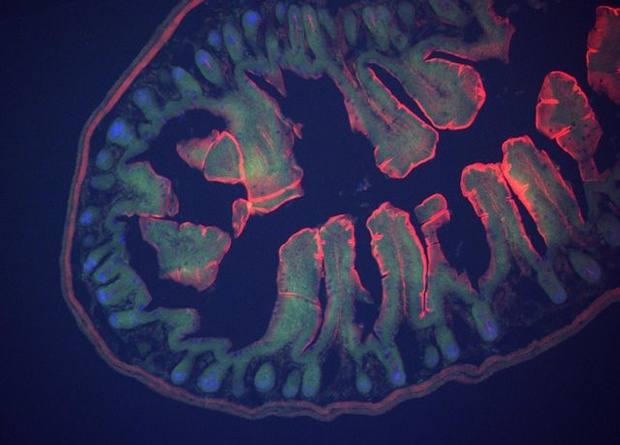

Пересадка фекальной микробиоты в капсулах помогла улучшить чувствительность к инсулину только тем пациентам, которые употребляли целлюлозу. Такие итоги клинического исследования опубликовали в Nature Medicine ученые из трех стран. Они проанализировали, как эффект лечения фекальной микробиотой в капсулах зависит от вида употребляемых пищевых волокон у людей с ожирением. Ученые считают, что целлюлоза помогает микроорганизмам дольше задерживаться в кишечнике и дает полезным бактериям преимущество в выживании.

Самые распространенные методы лечения ожирения — диета и физическая активность — не всегда справляются с проблемой. Тогда медики прибегают к другим методам, например препаратам. Эти лекарственные средства обычно содержат гормоны и имеют побочные эффекты, поэтому пациентам приходится отказываться от них. В последние годы изучался метод трансплантации фекальной микробиоты для лечения ожирения и расстройств метаболизма. Пересадка кала от здоровых доноров без лишнего веса помогала людям с ожирением похудеть, но эффект лечения был кратковременный. Скорее всего, это происходит потому, что со временем донорская микробиота исчезает из организма пациентов. У предыдущих исследований также были ограничения: они проводились на мужчинах с легкими нарушениями метаболизма и использовали инвазивные техники доставки донорской микробиоты, поэтому ученым необходимо отработать методику лечения на всех группах пациентов и усовершенствовать